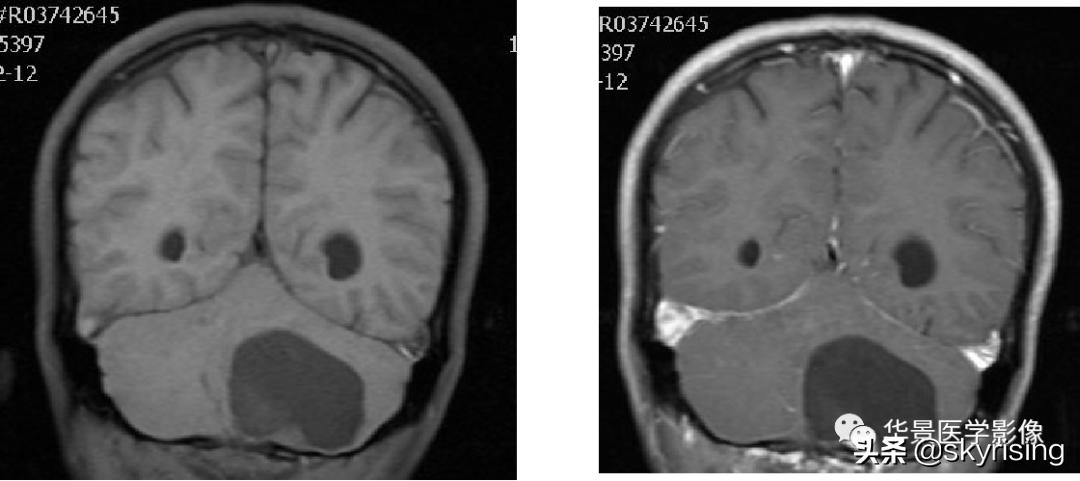

以下依次为T2WI、FLAIR、T1WI、增强、DWI及ADC:

上图白色箭头:小脑延髓池内延髓背侧不规则形团块影,小脑半球、延髓、第四脑室受压变形,所见诸脑室未见增宽。

蓝色箭头:延髓受压前后径变窄,T1信号减低,考虑合并水肿。

黄色箭头:病灶边缘见流空信号血管影。

小脑延髓池内见不规则异常信号影,呈长T1长T2信号,内部信号不均,边缘见稍粗大流空信号血管影,FLAIR少许片状低信号,增强呈明显强化,DWI不均质低信号,ADC不均质高信号。小脑半球、延髓、第四脑室受压变形。临近延髓变窄,呈长T1长T2信号。

总体以不规则实性占位病变,临近走行血管流空信号影,增强明显强化,DWI低信号为特点。